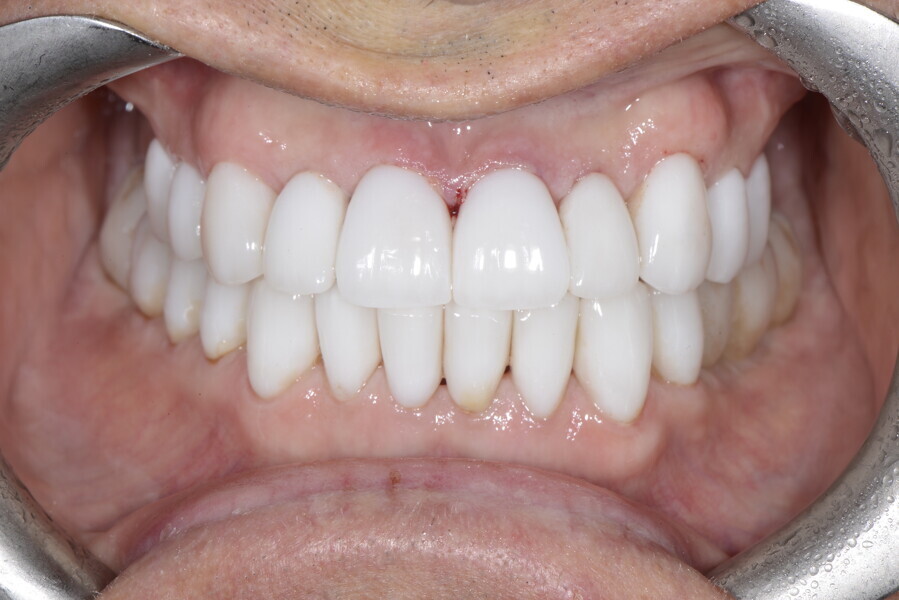

After the first phase of aligner treatment, we had achieved better inter-arch coherence, better maxillary arch expansion, and some space for improving the anterior tooth proportions restoratively (Fig. 19). We then temporarily restored the anterior teeth directly with composite, closing the spaces, improving the tooth proportions and further increasing the maxillary arch expansion (Fig. 20). We used restorative arch expansion to reduce the orthodontic destabilisation of the teeth to achieve the correct inter-arch coherence and retain the teeth in the cortical bone.38 A refinement aligner phase was undertaken to improve the final alignment of the gingival zenith and to improve the inter-arch coherence (Fig. 21). The periods of the first orthodontic phase and of the refinement were used to augment the mandibular and maxillary bone and to place the implants (Fig. 22). At the end of the orthodontic treatment, the case was finalised with ceramic veneers in the anterior area and temporary restorations on the implants in the posterior area (Figs. 23–26).

The provisional phase of about four months was important to allow the peri-implant tissue to mature and to teach the patient to chew correctly with chewing gum, cotton rolls and silicone masticatory sticks. This is fundamental training for the patient to achieve the correct alternating unilateral masticatory cycle needed to obtain the ideal rehabilitation of the masticatory system. We wanted the patient to achieve ideal masticatory and swallowing function. After sufficient rehabilitation time, we finalised the case with posterior zirconia crowns screwed on to the implants (Fig. 27).26

Our ideal final rehabilitation goals were:

• posterior stability;

• inter-arch coherence and U-shaped arches;

• anterior freedom during mastication;

• minimum disclusion vertical dimension;

• alternating unilateral masticatory cycle;

• physiological swallowing and high tongue posture against the palate; and

• mandibular disclusion advancing the mandible freely.

For maintenance purposes, after prosthetic finalisation, the patient was to carry on with the Froggymouth therapy and to use the Ri.P.A.Ra. for physiotherapeutic exercises and mastication training (Fig. 28). It was strongly recommended that the patient wear a mandibular occlusal splint during sleep. This occlusal splint was designed with disclusion guides to advance the mandible and ensure balanced contralateral support (Fig. 29).11, 39 We achieved an aesthetic appearance with adequate inter-arch coherence and a better cephalometric result (Figs. 30 & 31).